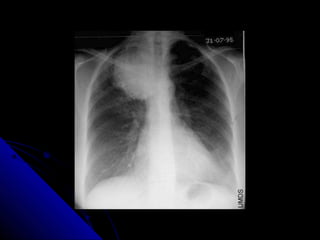

PPlleeuurraall eeffffuussiioonn

AA pplleeuurraall eeffffuussiioonn iiss ssiimmppllyy aa ccoolllleeccttiioonn ooff fflluuiidd

bbeettwweeeenn tthhee vviisscceerraall pplleeuurraa aanndd tthhee ppaarriieettaall

pplleeuurraa.. TThhiiss fflluuiidd ccoolllleeccttiioonn mmaayy bbee sseerroouuss

((pplleeuurraall eeffffuussiioonn)),, bblloooodd ((hheemmootthhoorraaxx)),, oorr ppuuss

((eemmppyyeemmaa))..

UUpprriigghhtt PPAA ffiillmm:: sshhaappee,, ddiissttrriibbuuttiioonn..

LLaatteerraall ffiillmm:: ppoosstteerriioorr CCPP rreecceessss..

SSuuppiinnee ffiillmm..

LLaatteerraall ddooccuubbiittuuss ffiillmm..